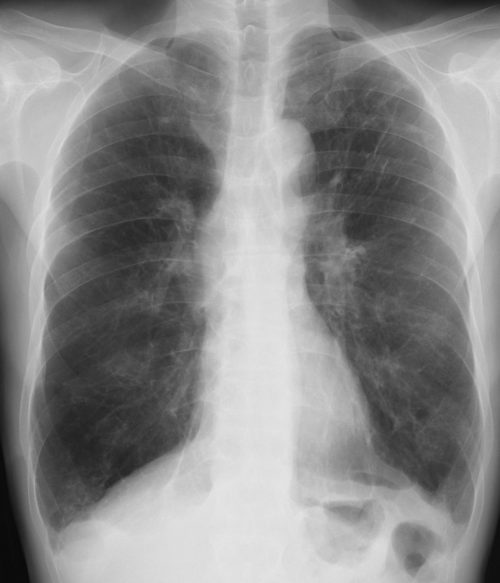

[正常例] 肺炎(軽症)を疑う経過の時、その鑑別は時に困難なことがある。

[肺炎例]マイコプラズマ肺炎